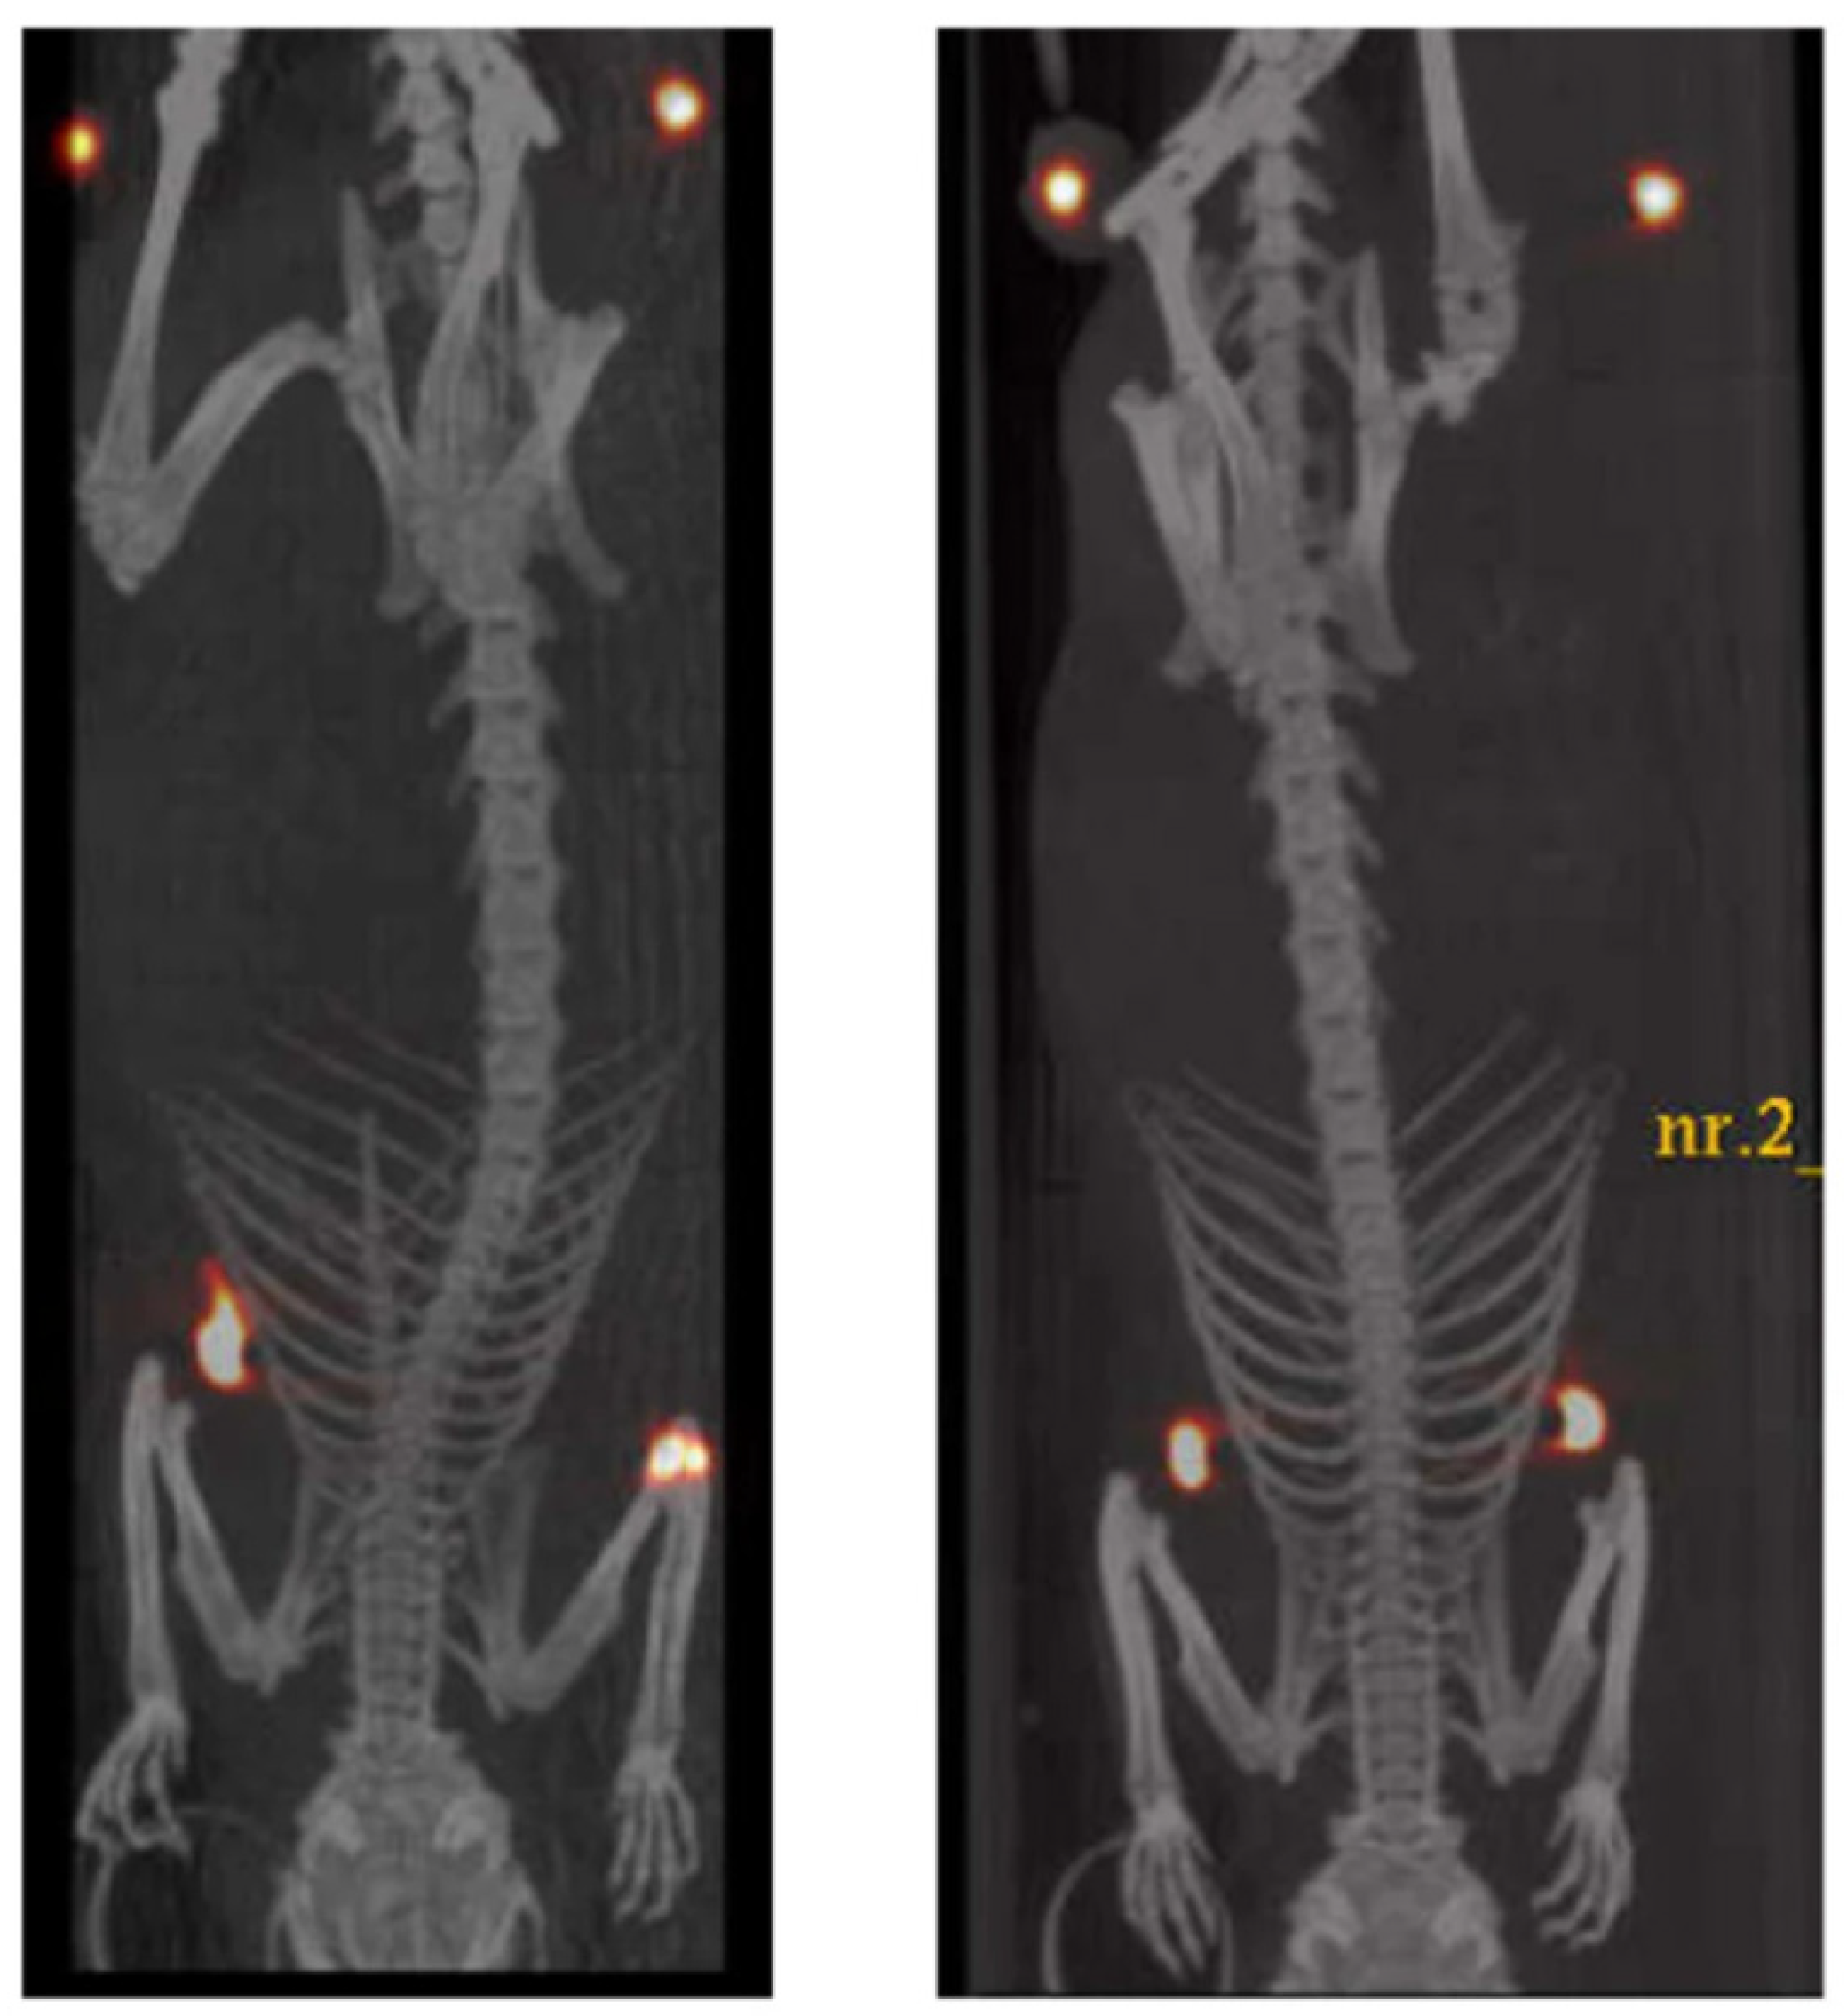

Among dual imaging modalities, the synergistic combination of MRI with SPECT and/or PET is likely to become the next generation of dual-modality scanners in medical imaging for accurate diagnoses, thanks to the sensitive and quantifiable signal of SPECT/PET and the high soft-tissue resolution of MRI. Moreover, since the use of SPIONs in the MRI technique could cause the accumulation of high iron loads related to their use in localized areas of the body, the identification of alternative biocompatible NPs having the same efficacy and lower iron content has become an important need. In this context, a valuable contribution was derived from Adamiano et al. [42] with the preparation of iron-doped hydroxyapatite (FeHA) NPs and their characterization as MRI imaging contrast agents along with a proof of concept of their use as scintigraphy imaging agents for PET and SPECT following the surface functionalization of FeHA NPs with [99mTc]-medronic acid (MDP). In this work, Adamiano et al. compared the diagnostic properties of their FeHA NPs with those of Endorem®, which is an FDA-approved SPION formulation, already used for the diagnosis of hepatic focal lesions. Endorem® consists of very small (<5 nm) round-shaped electron dense NPs, while FeHA NPs consist of small isometric crystals of about 5–10 nm aggregated in needle-like NPs having a length of 70–100 nm and width of 15–20 nm. FeHA and Endorem® in HEPES buffer at pH 7.4 showed negative zeta potential of –44.1 ± 0.9 mV and –25.0 ± 0.2 mV, respectively, and the hydrodynamic diameter size distributions recorded for FeHA and Endorem® were 179.1 ± 3.2 nm and 105.2 ± 2.0 nm respectively, with a high degree of poly-dispersity (PDI = 0.35) for Endorem®, due to the presence of relevant aggregates within the dextran matrix, and a lower PDI of 0.20 for FeHA. Moreover, the authors showed that, after intravenous injection in vivo in mice at a low iron dose (1 mg kg−1), the FeHA NPs displayed higher contrast enhancement and longer resistance in the liver, justifying these phenomena with the high transversal relaxation rate and the higher quantity of FeHA NPs that had been administered with respect to Endorem® to reach the same iron dose, as the two materials vehiculated different amounts of iron (9.7 vs. 71.0 w/w%). FeHA NPs were found to enhance the negative contrast also in spleen and renal cortex tissues, while on the contrary, Endorem® was detected in significant concentration only in the liver. Moreover, to demonstrate the potential use of FeHA NPs as multimodal MRI-PET/SPECT imaging agents, scintigraphy/X-ray fused imaging and ex vivo studies were conducted confirming the main uptake of FeHA NPs in the liver and secondarily in other organs in which other cells of the mononuclear phagocyte system (MPS) are located, as detected by MRI. Further in vitro and in vivo studies on FeHA long-term cytotoxicity along with in vivo validation of SPECT MRI detection are necessary; however, these NPs seem to be promising imaging agents for MRI-T2 and PET-SPECT, in order to design new theranostic agents for personalized medical applications.